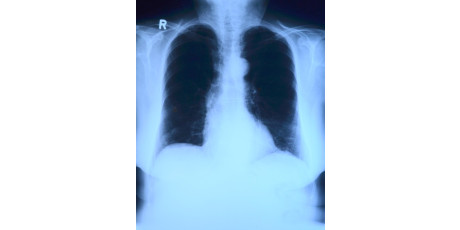

Infiltraat op thoraxfoto geen gouden standaard voor pneumonie

Een infiltraat op een thoraxfoto wordt regelmatig niet bevestigd bij een beoordeling door een tweede radioloog. Onderzoekers uit Maastricht hebben thoraxfoto's van 243 patiënten met een lageluchtweginfectie door 2 radiologen laten beoordelen. Bij 90% van de beoordelingen bestond overeenstemming …